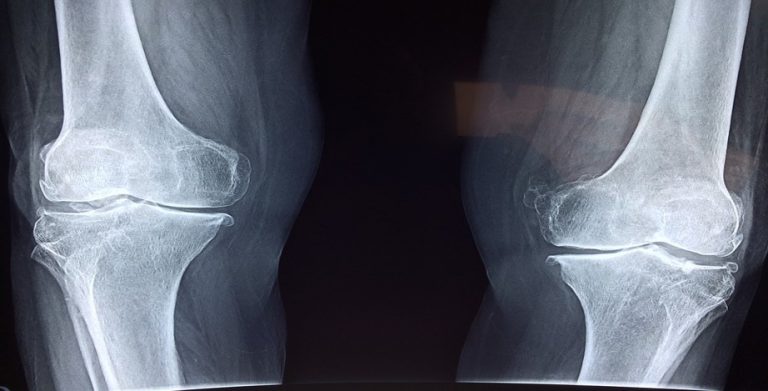

- Knee replacement includes resurfacing the femur, tibia, and the patella. Typically, an additional medical plastic spacer is put between the prosthesis parts in order to improve the properties of the gliding surface.